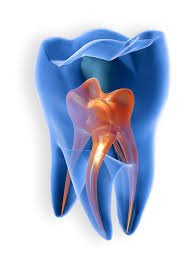

Root Canal treatment

Save your natural tooth with a painless root canal treatment. Ideal for treating deep cavities and infections, ensuring long-term dental health and pain relief.